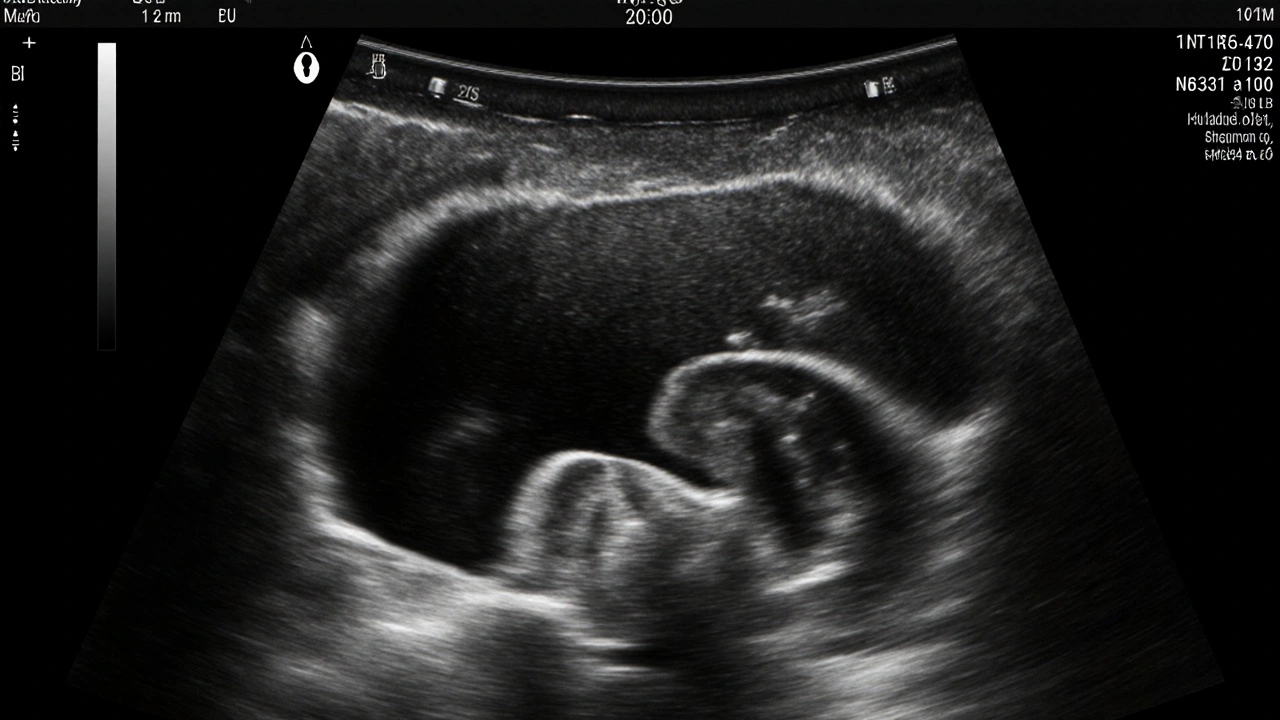

Ultrazvuk během těhotenství není jenom zábava, kdy se díváte, jak vaše dítě má ruce a nožky. Je to důležitý nástroj, který může pomoci odhalit některé vrozené vady už v rané fázi. Jednou z nejčastějších otázek, které si těhotné ženy kladou, je: jak se na ultrazvuku pozná Downův syndrom? Odpověď není jednoduchá - ultrazvuk neříká s jistotou, že dítě má Downův syndrom, ale ukazuje známky, které mohou vést k dalšímu vyšetření.

Na standardním ultrazvuku v 11. až 14. týdnu těhotenství (tzv. nukleární skríning) se lékaři dívají na několik konkrétních znaků. Ty nejsou samy o sobě důkazem Downova syndromu, ale zvyšují pravděpodobnost, že by mohl být přítomen.

• Zvětšená nukleární transparentnost (NT) - to je vrstva tekutiny pod kůží na krku plodu. Pokud je tato vrstva silnější než obvykle (např. více než 3 mm), zvyšuje se riziko chromozomálních poruch, včetně Downova syndromu.

• Chybějící nebo malý nosní kost - u zdravých plodů je nosní kost viditelná již kolem 12. týdne. U plodů s Downovým syndromem je často příliš malá nebo úplně neviditelná.

• Zkrácené paže a stehna - některé kosti plodu mohou být kratší než by měly být pro daný věk těhotenství. To není vždy problém, ale v kombinaci s jinými znaky může být indikací.

• Nepravidelný tvar srdce nebo srdeční vady - přibližně 40 % plodů s Downovým syndromem má nějakou srdeční vadu, kterou lze někdy detekovat na ultrazvuku.

• Prodloužená záda - někdy se pozoruje zvýšená tloušťka kůže na zádech plodu, což může být spojeno s větším rizikem chromozomální poruchy.

Tyto znaky se neobjevují u všech plodů s Downovým syndromem. Někteří plody je mají, jiní ne. A naopak - některé zdravé plody mohou mít jeden nebo dva z těchto znaků, aniž by měly jakoukoli poruchu. Proto je důležité pochopit: ultrazvuk ukazuje riziko, ne diagnózu.

Nejlepší čas na detekci známek Downova syndromu je mezi 11. a 14. týdnem těhotenství. V tomto období je nukleární transparentnost nejvíce viditelná a nosní kost se nejčastěji vyvinula. Pokud se ultrazvuk dělá později, například v 20. týdnu, může být už pozdě - některé znaky už nejsou tak jasné, a přesnější testy jako NIPT by měly být provedeny dříve.